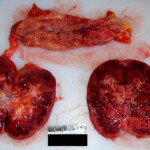

CHINA A young Chinese woman was given the wrong medication and died as a result. A detailed autopsy was performed on her. You can see her individual organs.